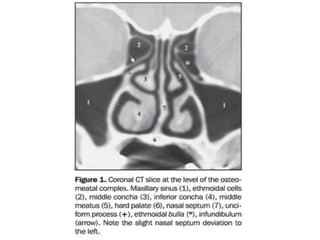

OSTEOMEATAL

COMPLEX

• Common channel that links frontal sinus, ant. and

middle ethmoid sinus, and max sinus to middle

meatus  allows air flow and mucociliary drainage 

needs to be patent for drainage of secretions in

sinusitis

OSTEOMEATAL COMPLEX •Common channel that links frontal sinus, ant. and middle ethmoid sinus, and max sinus to middle meatus  allows air flow and mucociliary drainage  needs to be patent for drainage of secretions in sinusitis